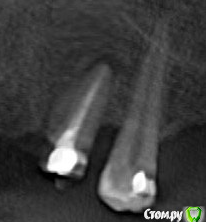

alex_ddd Опубликовано 29 июля, 2016 Автор Поделиться Опубликовано 29 июля, 2016 Ну, вот сегодняшний снимок 24 Ссылка на комментарий

alex_ddd Опубликовано 29 июля, 2016 Автор Поделиться Опубликовано 29 июля, 2016 Попытка 2 Ссылка на комментарий